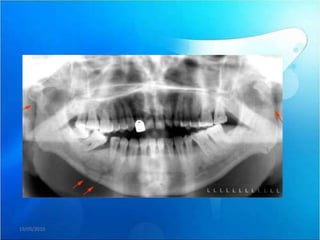

En la radiografía panorámica observamos la alteración morfológica de ambos

cóndilos mandibulares y la presencia de imágenes radiopacas hacia medial de

ambas articulaciones compatibles con probables fragmentos óseos libres.